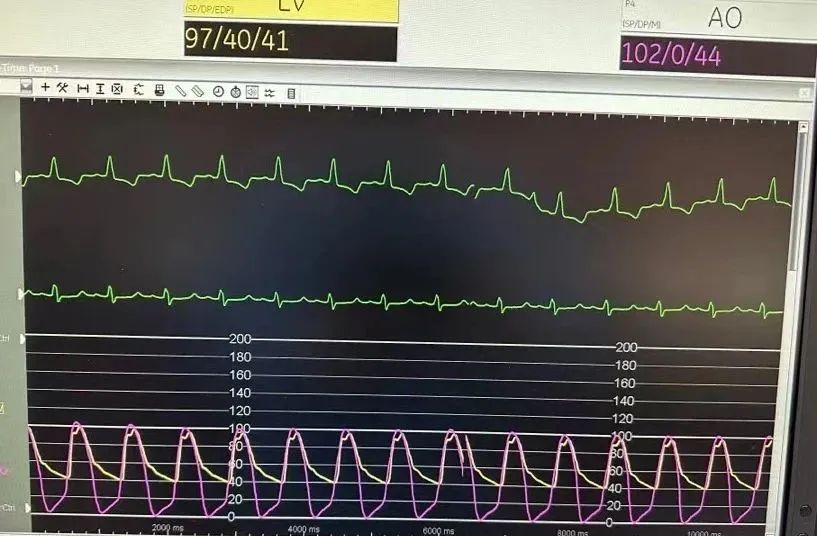

术后测压

术后压差

术后患者跨瓣压差接近0,无瓣周漏,术前由主狭造成的不适症状均得到明显改善,手术圆满成功!